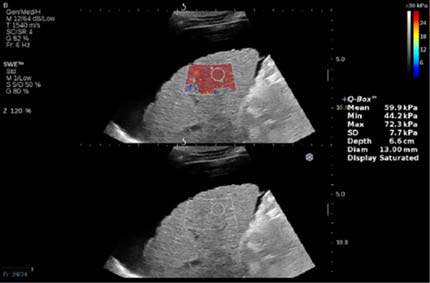

Представляем ряд клинических примеров, демонстрирующих определение степени фиброза печени с помощью SWE у беременных с HBV- и HCV-инфекциями (рис. 1–5).

Рис. 5. Беременная В.Е., G3P3A0, позитивна по вирусу гепатита С, результат сдвигововолновой эластографии печени: METAVIRSTAGE — F4

Обследование проводили в положении пациентки на спине с уклоном влево. Датчик располагали в восьмом-девятом межрёберном промежутке по правой передней и задней подмышечной линии. Плотность ткани определяли в правой доле на бессосудистом участке на глубине 2 см от капсулы, результаты выражали в килопаскалях. Полученные показатели плотности тканей оценивали по шкале METAVIR: <7,1 кПa — F0–F1; 7,1–7,9 кПa — F2; 8,0–10,4 кПa — F3; >10,4 кПa — F4), где F0 — отсутствие фиброза; F1 — расширение портального тракта без септ; F2 — портальный фиброз с небольшим количеством сформированных септ; F3 — портальный фиброз с формированием множественных септ; F4 — цирроз печени.